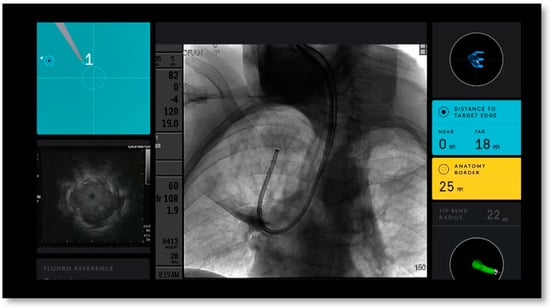

| Radial EBUS used during ENB | 42 (100%) |

| Fluoroscopy used during ENB | 42 (100%) |